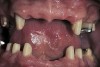

Figure 20  Periodontally hopeless teeth #8 through #10 were extracted and socket preservation protocols completed.

Figure 20